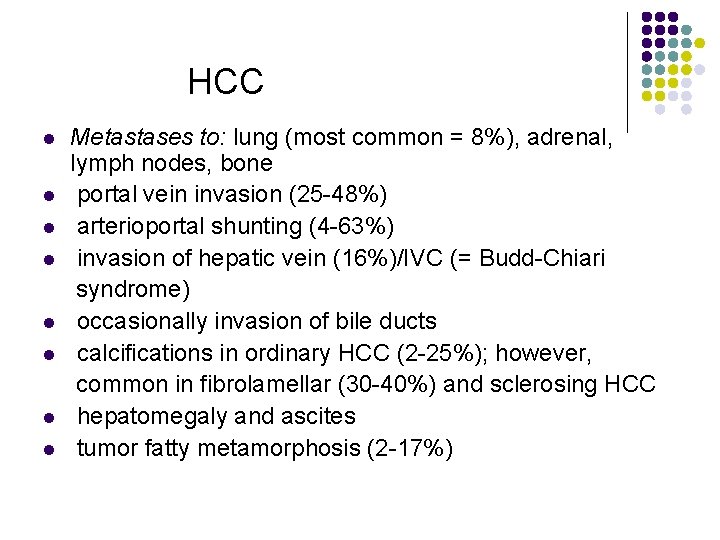

HCC l l l l Metastases to: lung (most common = 8%), adrenal, lymph nodes, bone portal vein invasion (25 -48%) arterioportal shunting (4 -63%) invasion of hepatic vein (16%)/IVC (= Budd-Chiari syndrome) occasionally invasion of bile ducts calcifications in ordinary HCC (2 -25%); however, common in fibrolamellar (30 -40%) and sclerosing HCC hepatomegaly and ascites tumor fatty metamorphosis (2 -17%)